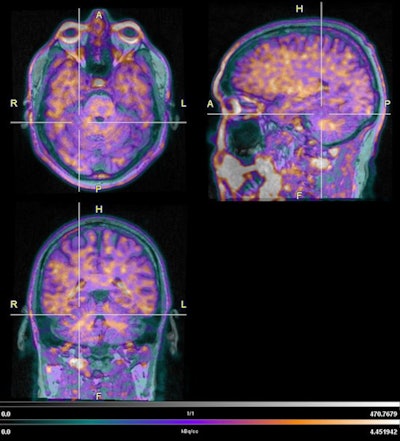

Given that cognitive impairment is quite common among Alzheimer's disease and dementia patients, Zhou and her colleagues created a pilot study to use PET/MRI to assess the extent and location of tau deposits, which have been linked to both conditions, across regions of the brain that included the amygdala and the inferior temporal and lateral occipital lobes.

Next up were PET/MRI scans (Biograph mMR, Siemens Healthineers), which began 80 to 100 minutes after injection of the PET radiotracer F-18 flortaucipir (Tauvid, Avid Radiopharmaceuticals), which has shown an ability to detect tau pathology and help differentiate between individuals with Alzheimer's disease and mild cognitive impairment and healthy controls. PET images then were registered to T1-weighted magnetization prepared rapid acquisition gradient echo (MPRAGE) MR images. Standardized uptake values (SUVs) across brain regions were partially corrected and normalized using the cerebellar gray matter.

While the researchers found nine responders (64%) met the criteria for preclinical Alzheimer's disease, only three responders (21%) had advanced to stage I-II Alzheimer's with abnormally high uptake in the entorhinal cortex. Most interestingly, Zhou and colleagues noted in their abstract that only one responder "had patterns consistent with stage III [Alzheimer's], and one had uptake in the temporal cortex consistent with advanced Alzheimer's, though not all regions expected to exhibit tau increases at stage IV were affected."